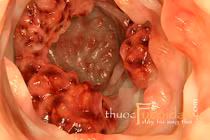

Ung thư đại tràng: Hành tây rất giàu chất xơ và việc tiêu thụ nhiều chất xơ thực vật giúp giảm nguy cơ ung thư đại trực tràng.

Ung thư thực quản và ung thư dạ dày: Ngoài ung thư đại tràng, ung thư tuyến tiền liệt, hành tây cũng làm giảm nguy cơ mắc ung thư thực quản và ung thư dạ dày. Một số nghiên cứu cho thấy cũng như các loại rau củ chi hành khác cũng có tác dụng này.